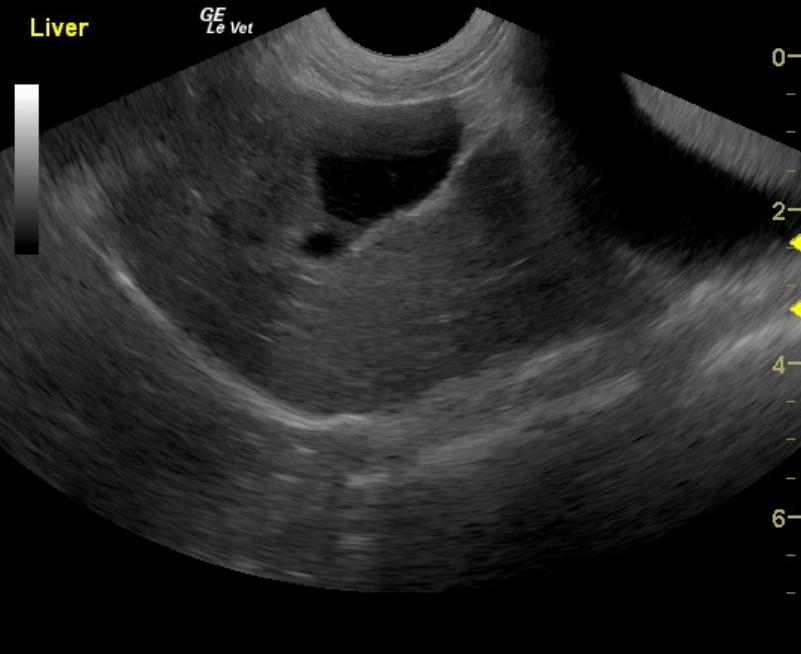

A 17-year-old neutered male DSH cat was presented to the emergency clinic with open-mouth breathing suspected to be secondary to stress/pain as the patient improved on analgesics. On a prior physical examination, an abdominal mass had been palpated.